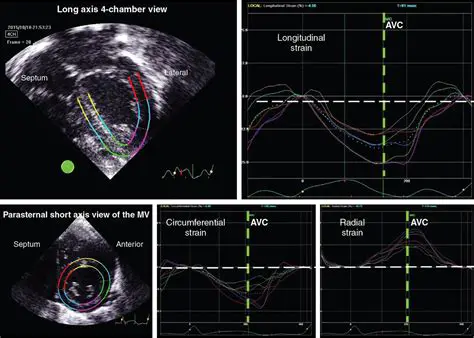

Understanding Doppler Placement